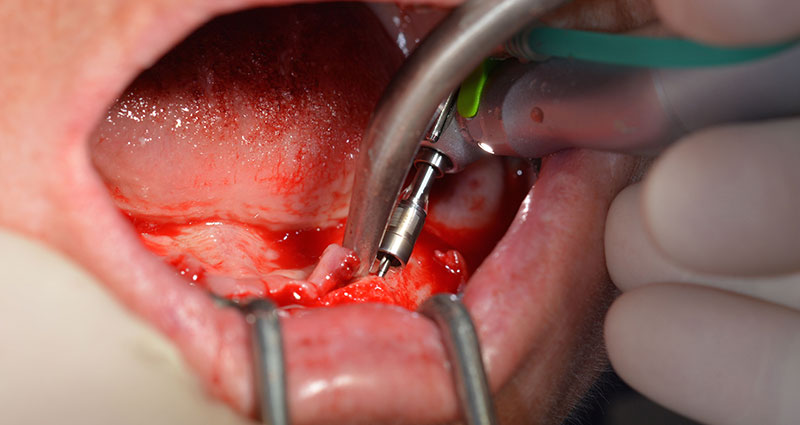

A questo punto si possono già intuire i vantaggi che garantisce Implantmed. Il protocollo chirurgico è già predefinito e gli strumenti sono collocati in posizione fissa. Le posizioni individuali possono essere selezionate premendo la lettera "P" con il controllo a pedale o tramite il display. La velocità predefinita è di 35.000 giri/min nella posizione 1 e, in questo caso, i numeri sono visualizzati sul display illuminato (Fig. 5 e 6).

Il protocollo chirurgico per il sistema di implantologia utilizzato (SKY, Bredent medical) prevede una velocità di 1.200 giri/min per la perforazione pilota (Fig. 7 - 9).